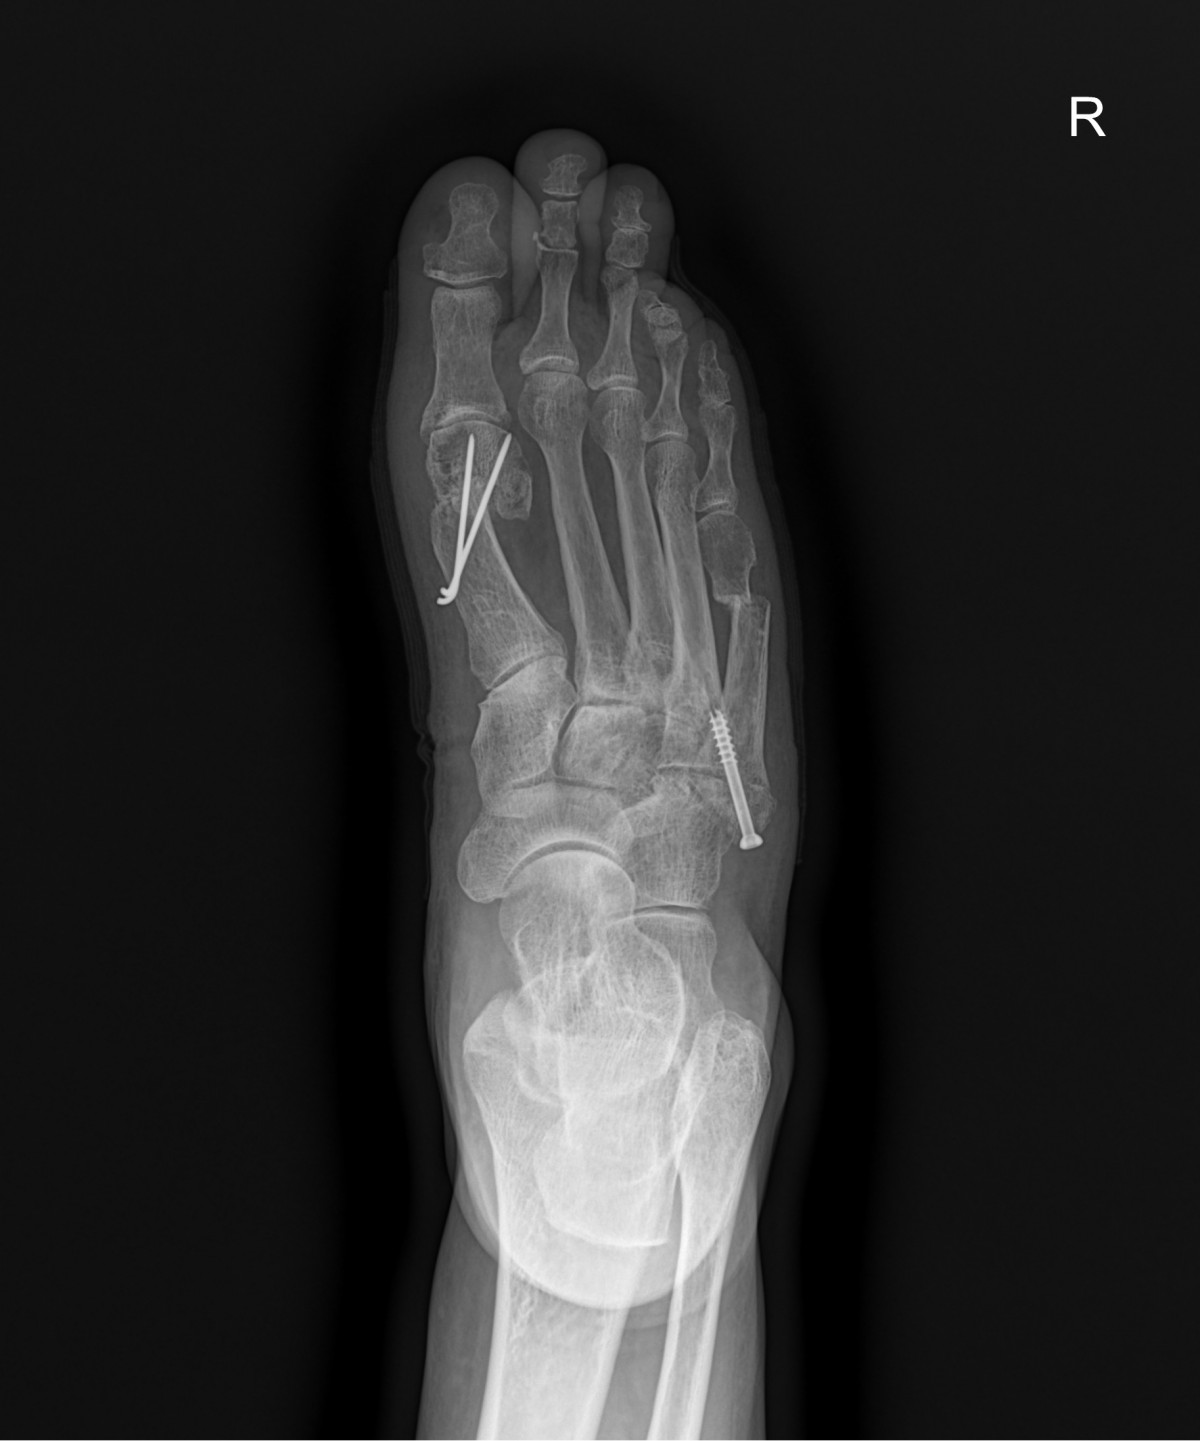

이재상원장님 무지외반증 및 발등 골절 수술 김순O 환자

dae765e4d9ac96aee867c9d6292d8784_1758002464_0921.jpg